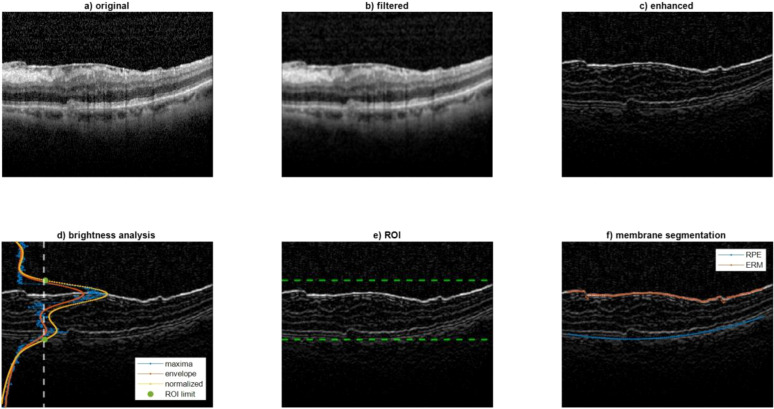

Methods: A retrospective analysis was conducted on 9 patients who underwent peeling surgery for idiopathic, symptomatic, and progressive epiretinal membrane. The RI assesses the displacement of vascular crossings in time from a fixed point, which is the retinal pigmented epithelium. This updated iteration integrates infrared images paired with OCT scans instead of OCTA.